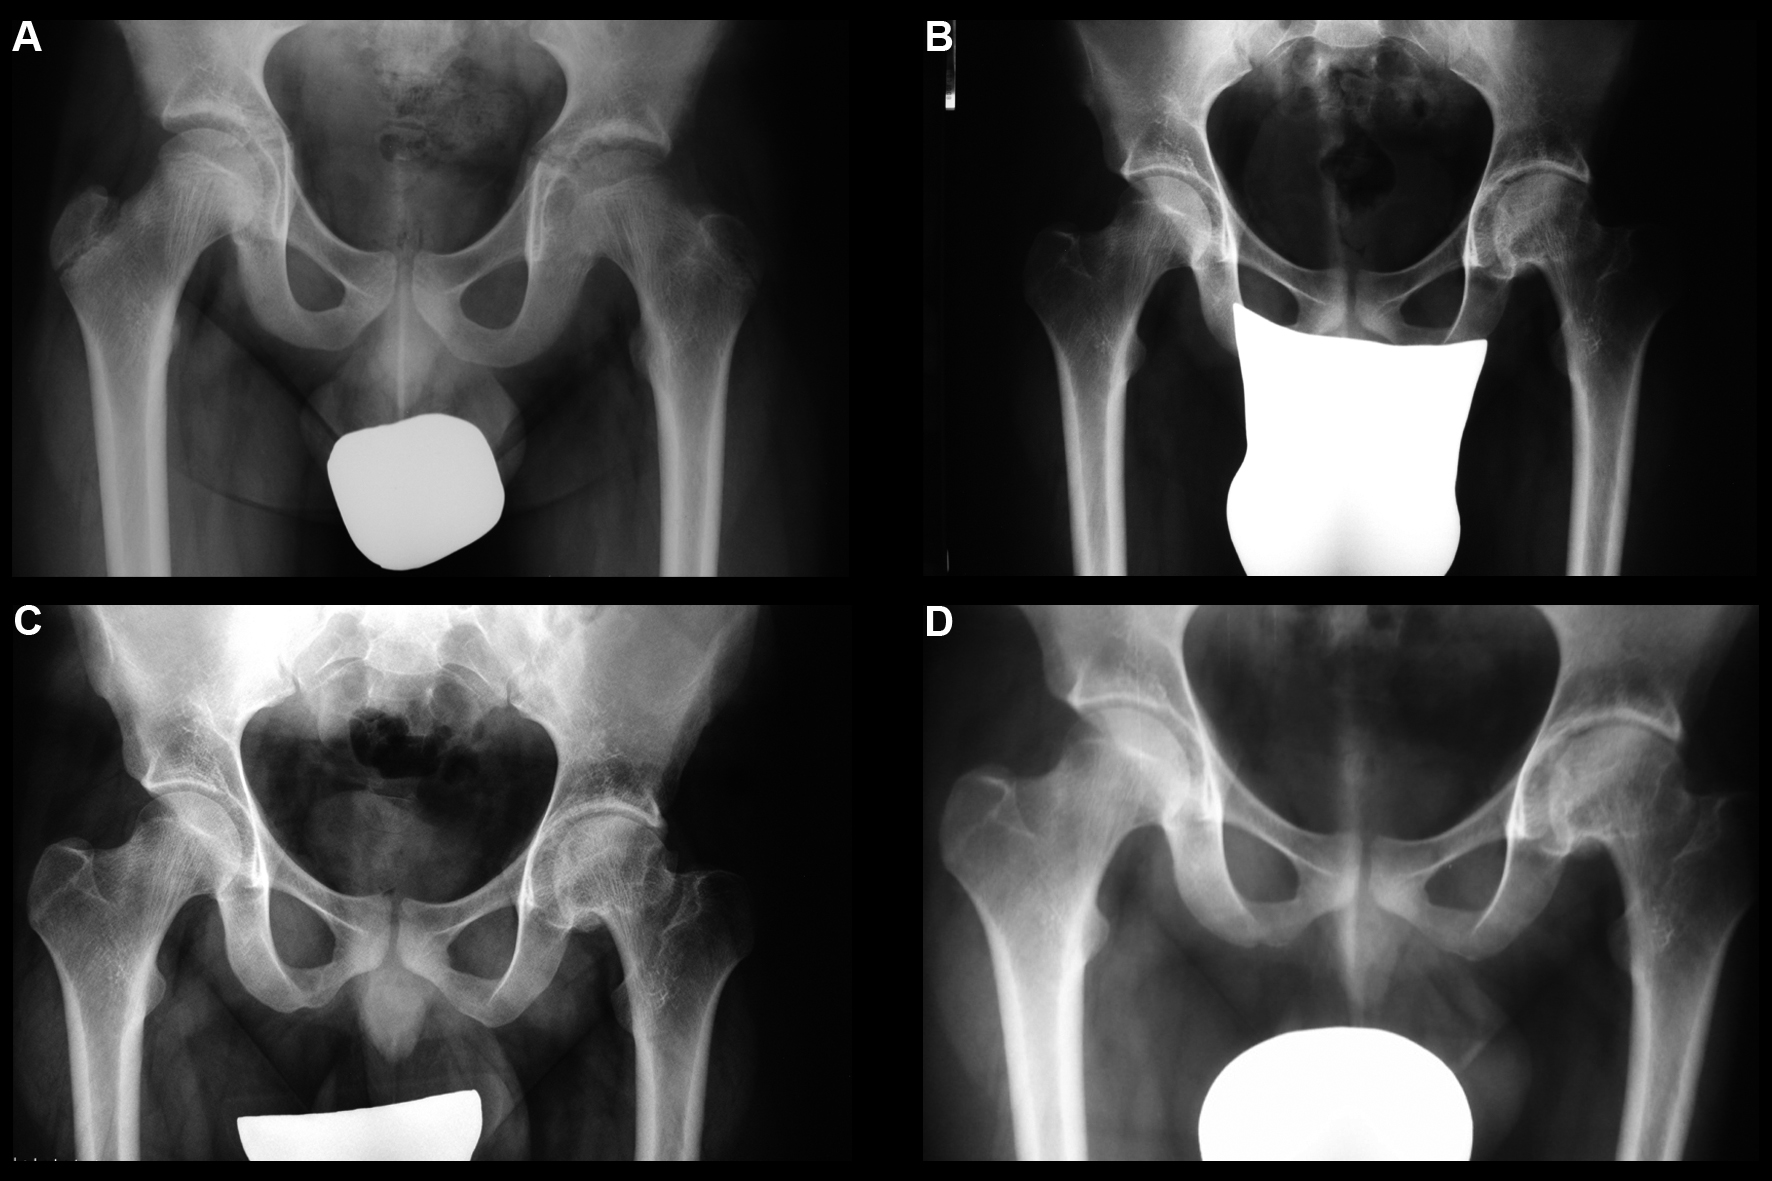

La condrolisis idiopática de cadera es una rara condición que se presenta durante la adolescencia. Se caracteriza por dolor y cojera producidos por una pérdida acelerada del cartílago articular con una disminución del grado de movilidad llegando a rigidez. La historia va desde la resolución espontánea completa a la anquilosis. El tratamiento recomendado actualmente es el conservador. Se presenta el caso clínico de un paciente de 11 años de edad con un cuadro clínico de 2 años de evolución tórpida de dolor inguinal izquierdo acompañado de cojera y rigidez. Se instauró reposo, descarga, analgésicos y rehabilitación sin mejoría inicial. Posteriormente recibió tratamiento conservador con AINE, periodos de descarga de la extremidad, tracción blanda hospitalaria, tracción ambulatoria nocturna y rehabilitación, recuperando la movilidad y marcha normal 6 años después del inicio de los síntomas. Catorce años más tarde el paciente hace una vida normal, asintomático y con movilidad simétrica de ambas caderas.